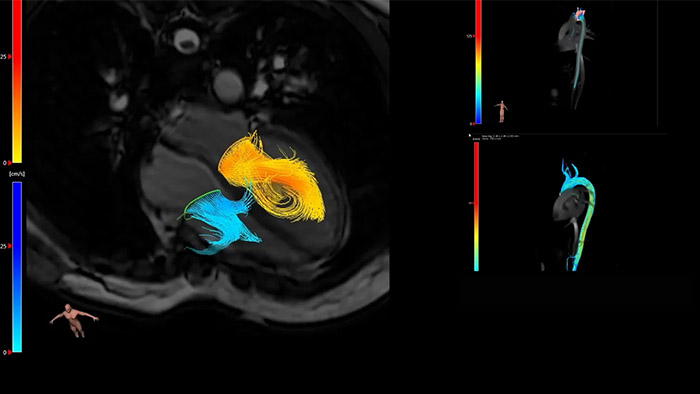

IntelliSpace Portal MR Caas5,6 4D Flow post-processing solution enables generation of 3D volume reconstructions, to visualise and evaluate blood flow in cardiovascular structures, including heart valves, chambers, and vessels, based on cardiovascular MR 4D Flow imaging.